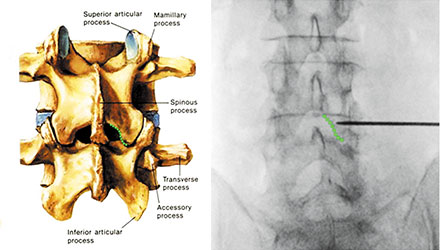

Diagram of inferomedial edge of the lamina

Target site – inferomedial edge of the lamina – is identified with fluoroscopy imaging.